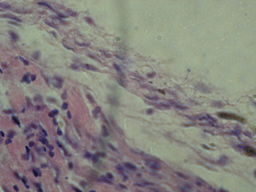

У трахеї інфікованих ПЕ виявлено запальні та деструктивні процеси, в які залучено всі шари слизової оболонки. Так, помірний набряк власно слизової оболонки був зафіксований після інокуляції ПЕ вакцинного штаму 1062 (рис. 4).

Рис.4. Гістологічні зміни трахеї ПЕ, інфікованих вакцинним штамом 1062

а) набряк слизової оболонки трахеї:

б) кровонаповнення судин слизової оболонки трахеї:

в) трахея ПЕ контрольної групи( фарбування гематоксилін-еозин, збільш..Х )

У той же час крім загальних ознак, призводить також до дегенерації епітеліального шару трахеї ПЕ. кровонаповнення судин власно слизової оболонки, відмічено, переродження епітеліальних клітин слизової оболонки трахеї

2.Вакцинний штам 1062 зумовлює запальні та деструктивні процеси в організмі ПЕ помірний набряк власно слизової оболонки трахеї та відшаровування епітеліальних клітин трахеї.